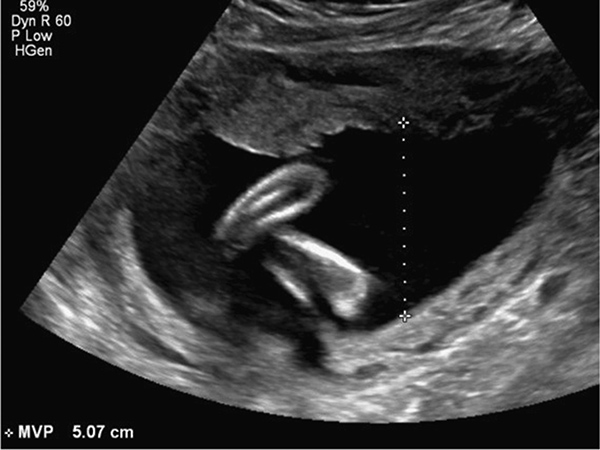

Chỉ số ối bình thường được viết tắt là AFI (Amniotic Fluid Index), là chỉ số về lượng ối trong bụng mẹ được bác sĩ đo trong quá trình khám thai theo từng tháng. Dựa vào những thông số khi siêu âm và đo lượng ối mà bác sĩ sẽ cho biết chỉ số ối bình thường hay bất thường.

Đo chỉ số ối bình thường bằng cách chia tử cung thành bốn buồng bằng hai đường cắt ngang và dọc qua rốn. Sau đó bác sĩ sẽ tiến hành đo từ góc sâu nhất của khoang ối trong mỗi buồng rồi tính tổng số đo để ra chỉ số ối bình thường.

Để biết chỉ số ối, mẹ bầu có thể so sánh chỉ số AFI của mình với bảng chỉ số tiêu chuẩn dưới đây:

| Chỉ số ối AFI (cm) | Mức độ | Lưu ý |

| Vô ối | Chỉ số ối quá thấp dẫn đến vô ối, lượng nước ối ít dẫn đến sinh non hoặc thai lưu | |

| Thiếu ối | Lượng ối quá thấp làm tăng tỷ lệ dị tật thai hoặc thai chậm phát triển | |

| 6cm – 12cm | Bình thường | Đây là chỉ số ối bình thường và mẹ bầu không cần lo lắng |

| 12cm – 20cm | Dư ối | Lượng nước ối nhiều hơn bình thường nhưng vẫn nằm trong tiêu chuẩn an toàn |

| >20cm | Đa ối | Chỉ số ối quá cao và có nguy cơ vỡ ối đột ngột, sinh sớm hoặc ngôi thai bất thường |